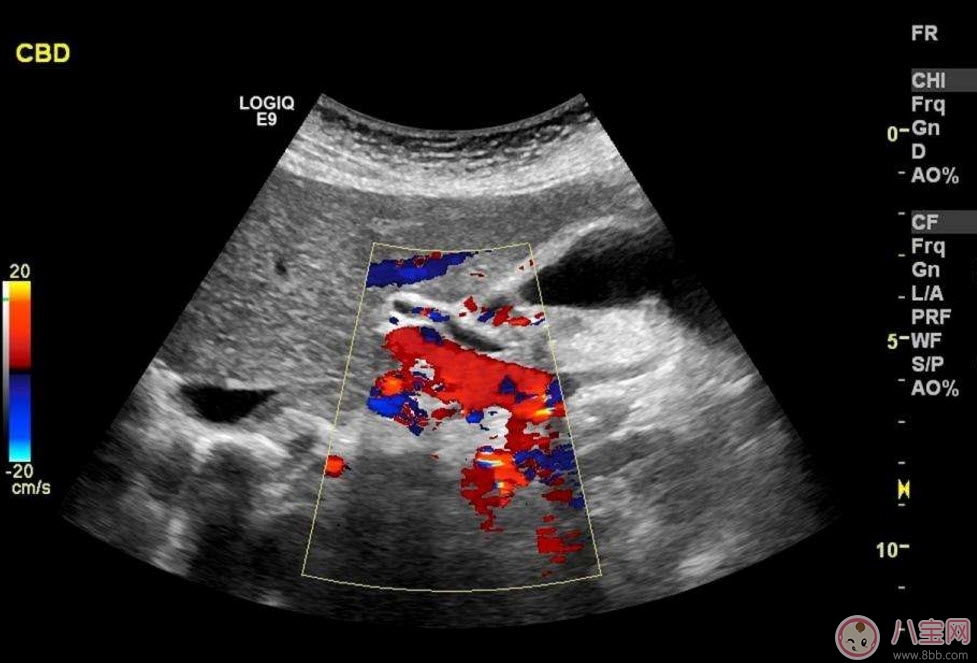

??B超也稱為二維超聲,分為黑白的和彩色的兩種。 彩超其實還是黑白的,彩超簡單的說就是高清晰度的黑白B超再加上彩色多普勒,既具有二維超聲結構圖像的優(yōu)點,又提供了血流動力學的豐富信息。彩超的分辨率會比一般黑白B超高一些,所以在需要做比較細致的檢查的時候,更多的醫(yī)生愿意通過彩超來檢查。例如,因為彩超能用彩色標注血流,所以當臍帶繞頸的時候就會看見寶寶的脖子上呈U形或者W形的血流,對是否臍帶繞頸也就一目了然了。目前用于產檢的超聲波一般都是二維的。

除了能觀察到通過B超觀察到的一切外,彩超能夠直觀成像,顯示更清晰,結果也更快速,可發(fā)現(xiàn)異常血流,為診斷胎兒先天性心臟缺陷提供了診斷依據(jù)。價格要比B超貴,大概在150元左右(會根據(jù)各地具體情況的不同而上下浮動)。二維彩超適用于整個孕期,特別是臨產前。二維彩超的圖像也并非就是彩色的,而是用彩色標注心臟、血流等指標,其實就是高清晰度的黑白B超再加上彩色多普勒。觀測到的圖像以紅藍兩色血流方向為主,面向探頭的呈現(xiàn)紅色,反之為藍色。這種技術能夠觀測到胎兒的血液流動情況,有利于及時發(fā)現(xiàn)胎兒的異常。比如,發(fā)現(xiàn)胎兒頸部有血流環(huán),則意味著發(fā)生了可導致窒息死亡的臍帶繞頸。